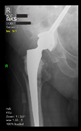

The radiological examination allowed us to verify the close bone-to-implant contact and the unchanged position of the implant during follow-up.

In all the cases operated with the above-described targeting procedure, the stems of the cups remained between the cortical bone surfaces without perforation of the linea terminalis, as shown by postoperative radiographs. There were no complicated surgical situations. In 16 cases, the wound healings were uneventful, and the hips were able to bear weight again after postoperative rehabilitation.